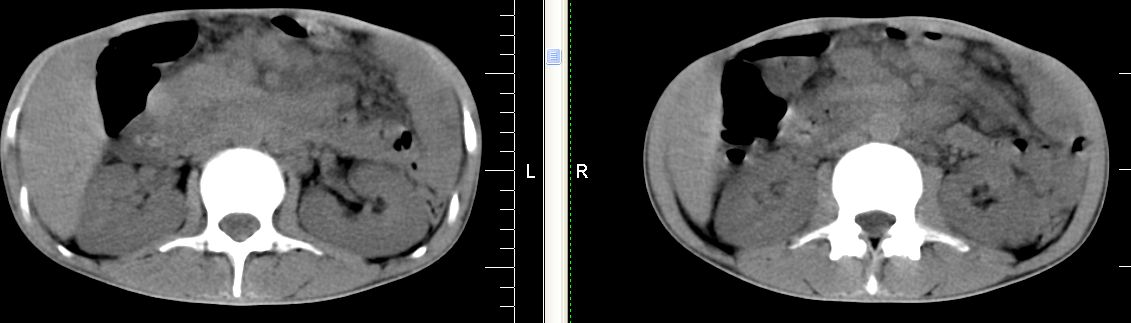

m 29 肺tb患者,目前诉下腹疼痛 t39度 腹韧,有压痛,可触及3x4cm包块

脾脏多发低密度灶,肠系膜及腹膜后见多发大小不等结节状影,右结肠旁沟见低密度影,结合病史考虑:脾结核,肠系膜及腹膜后淋巴结结核,少量腹水。

右侧结肠亦可见病变,腹膜后可见多发增大的淋巴结影,脾脏内示多个低密度结节灶,结合病史考虑结核性病变。

脾脏多发低密度灶,腹膜后及肠系膜根部多发淋巴结淋巴结肿大并部分相互融合,考虑tb.图象窗宽\\窗位没调整好,不清晰,另外,肠道准备亦不理想.

脾脏多发低密度灶,左侧肾上腺见块状病灶,密度不均,盲肠升结肠肠壁明显增厚,左下腹似可见肠壁增厚,肠系膜及腹膜后见多发大小不等结节状影,右结肠旁沟见低密度影,1淋巴瘤可能大,2结合病史考虑:脾结核,左侧肾上腺结核,肠系膜及腹膜后淋巴结结核,少量腹水待除外,